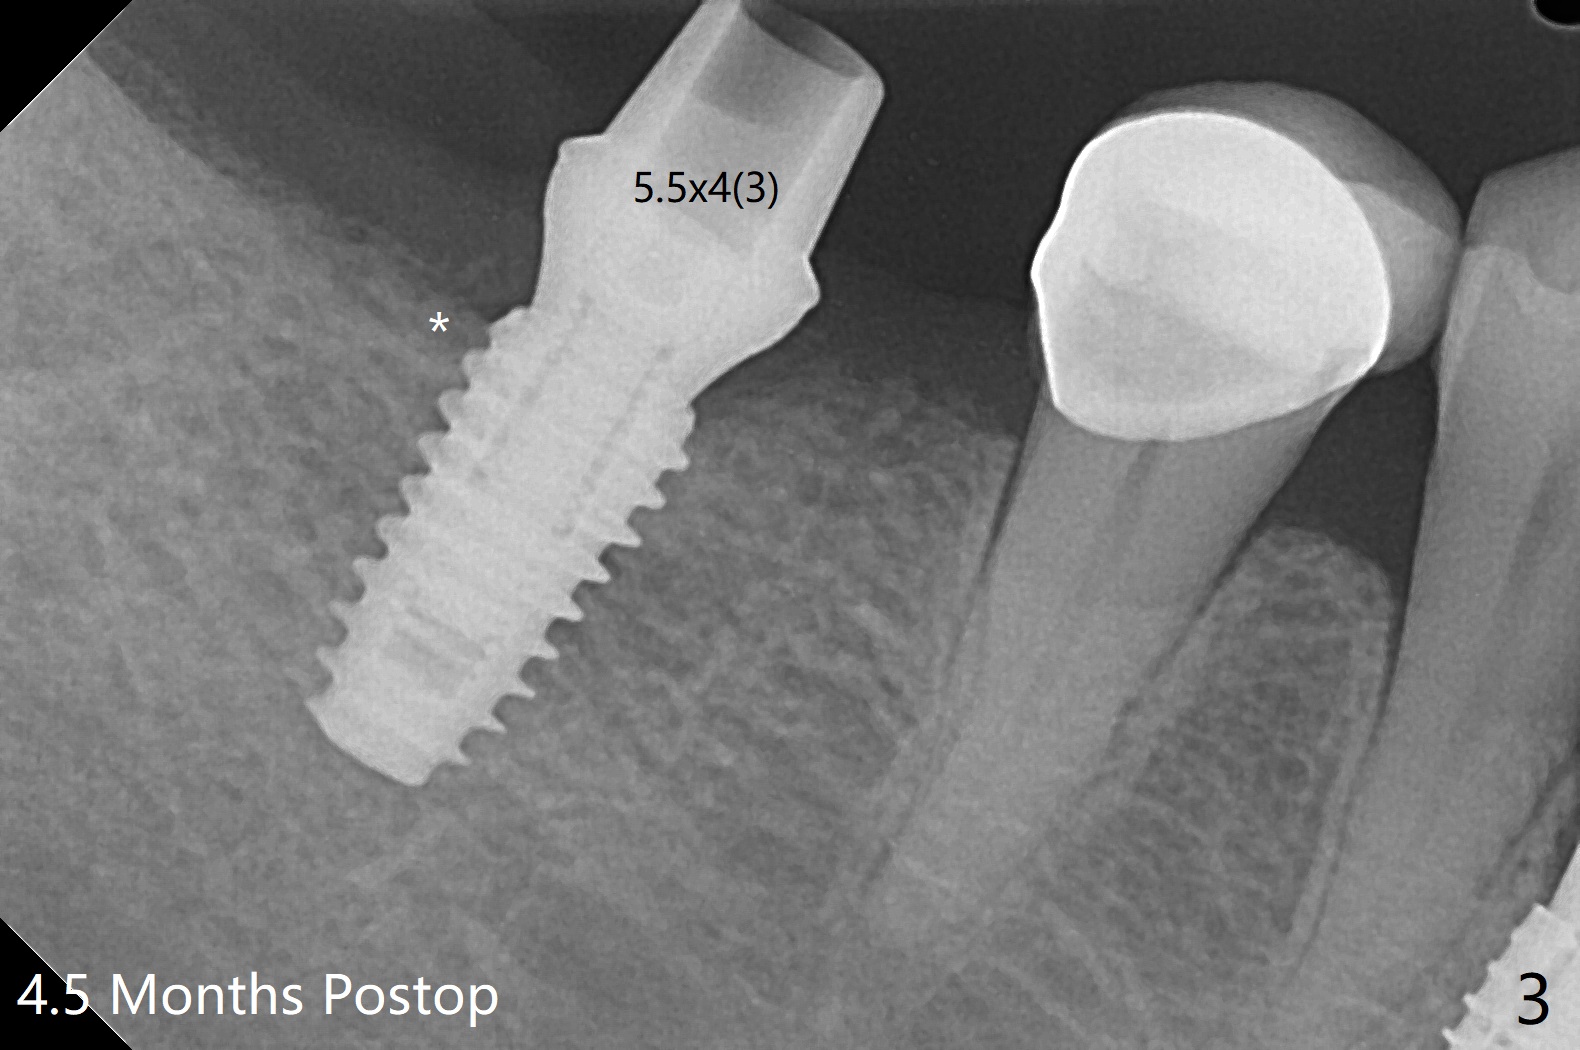

When the guide is seated for #30 implant, it appears that the tissue punch may remove all of the buccal keratinized gingiva. Therefore incision is made with flap reflection. The bigger advantage of flap surgery is that as the implant is placed, the lingual crest is found to be the lowest (which is the most likely to be neglected with flapless approach) so that bone graft can be easily placed. In contrast the mesial crest is the highest. For seating of a cemented abutment (Fig.1) and a healing abutment (Fig.2), profile drills (5.5 and 6.0 mm) have to be used, respectively. Following #31 extraction, Vanilla graft (minor portion) and Osteogen Plug (major portion, most likely no implant in the future) are placed, followed by GEM Cap and 4-0 Chromic Gut suture. After removing the healing abutment 4.5 months postop, a 5.5x4(3) mm cemented abutment is seated completely; it appears that the distal crest resorbs substantially (Fig.3 *). The access hole is distal as related to distal end guide (in fact #31 was used as distal stop before extraction) and radiation interference from #29 crown (Fig.4). The uneven mesial and distal crest may be the main reason for the deviation.